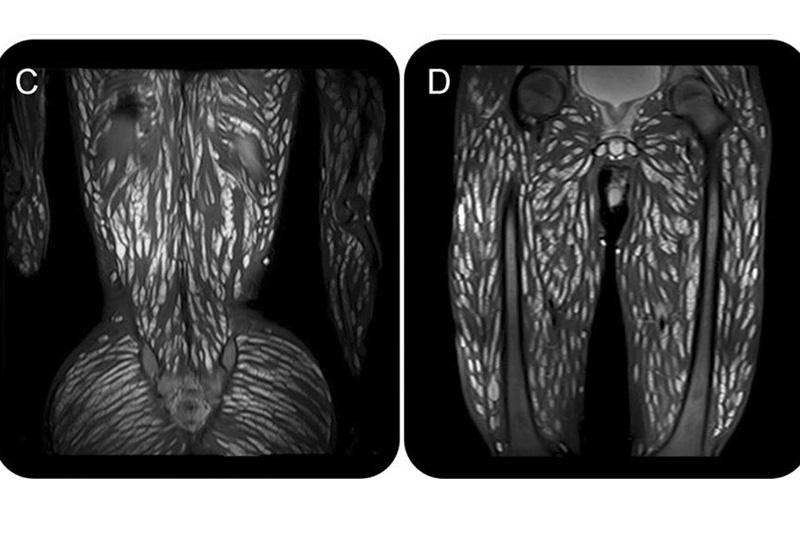

據外媒報道,泰國蘇拉納里科技大學醫學院寄生蟲研究中心(PDRC)在專頁分享一個病例,在病患的磁力共振掃瞄中,看到全身的白色小點,原來全是豬肉絛蟲(Pork tapeworm), 其腦部組織、頭頸、胸腹、側肌、脊柱、臀部、骨盆、四肢肌肉都有大量囊腫,確診患上囊尾蚴病。

醫生估計該名18歲男生曾經進食未徹底煮熟的豬肉,或是沒有完全清潔並帶有蟲卵的蔬果,飲不潔淨的水,甚至進食前未有洗手等原因,都可能有關。而患者接受類固醇、抗癲癇藥等治療後,情況慢慢好轉。